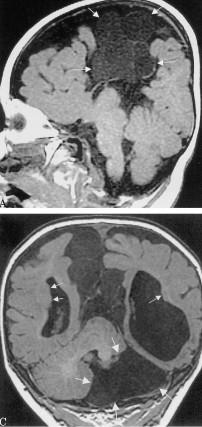

Malrotated hypoplastic vermis, with vertical primary fissure.

“OPEN” fastigial point of the fourth ventricle. Hypoplastic cerebellar hemispheres.

Enlarged posterior fossa

Cystic dilatation 4th ventricle

Uplifted tentorium, TSV sinus, torcula

“torcula-lambdoid inversion” with torcula above the lambdoid suture

Agenetic or hypogenetic vermis with “vermian tail, pushed upward

Cerebellar hypoplasia